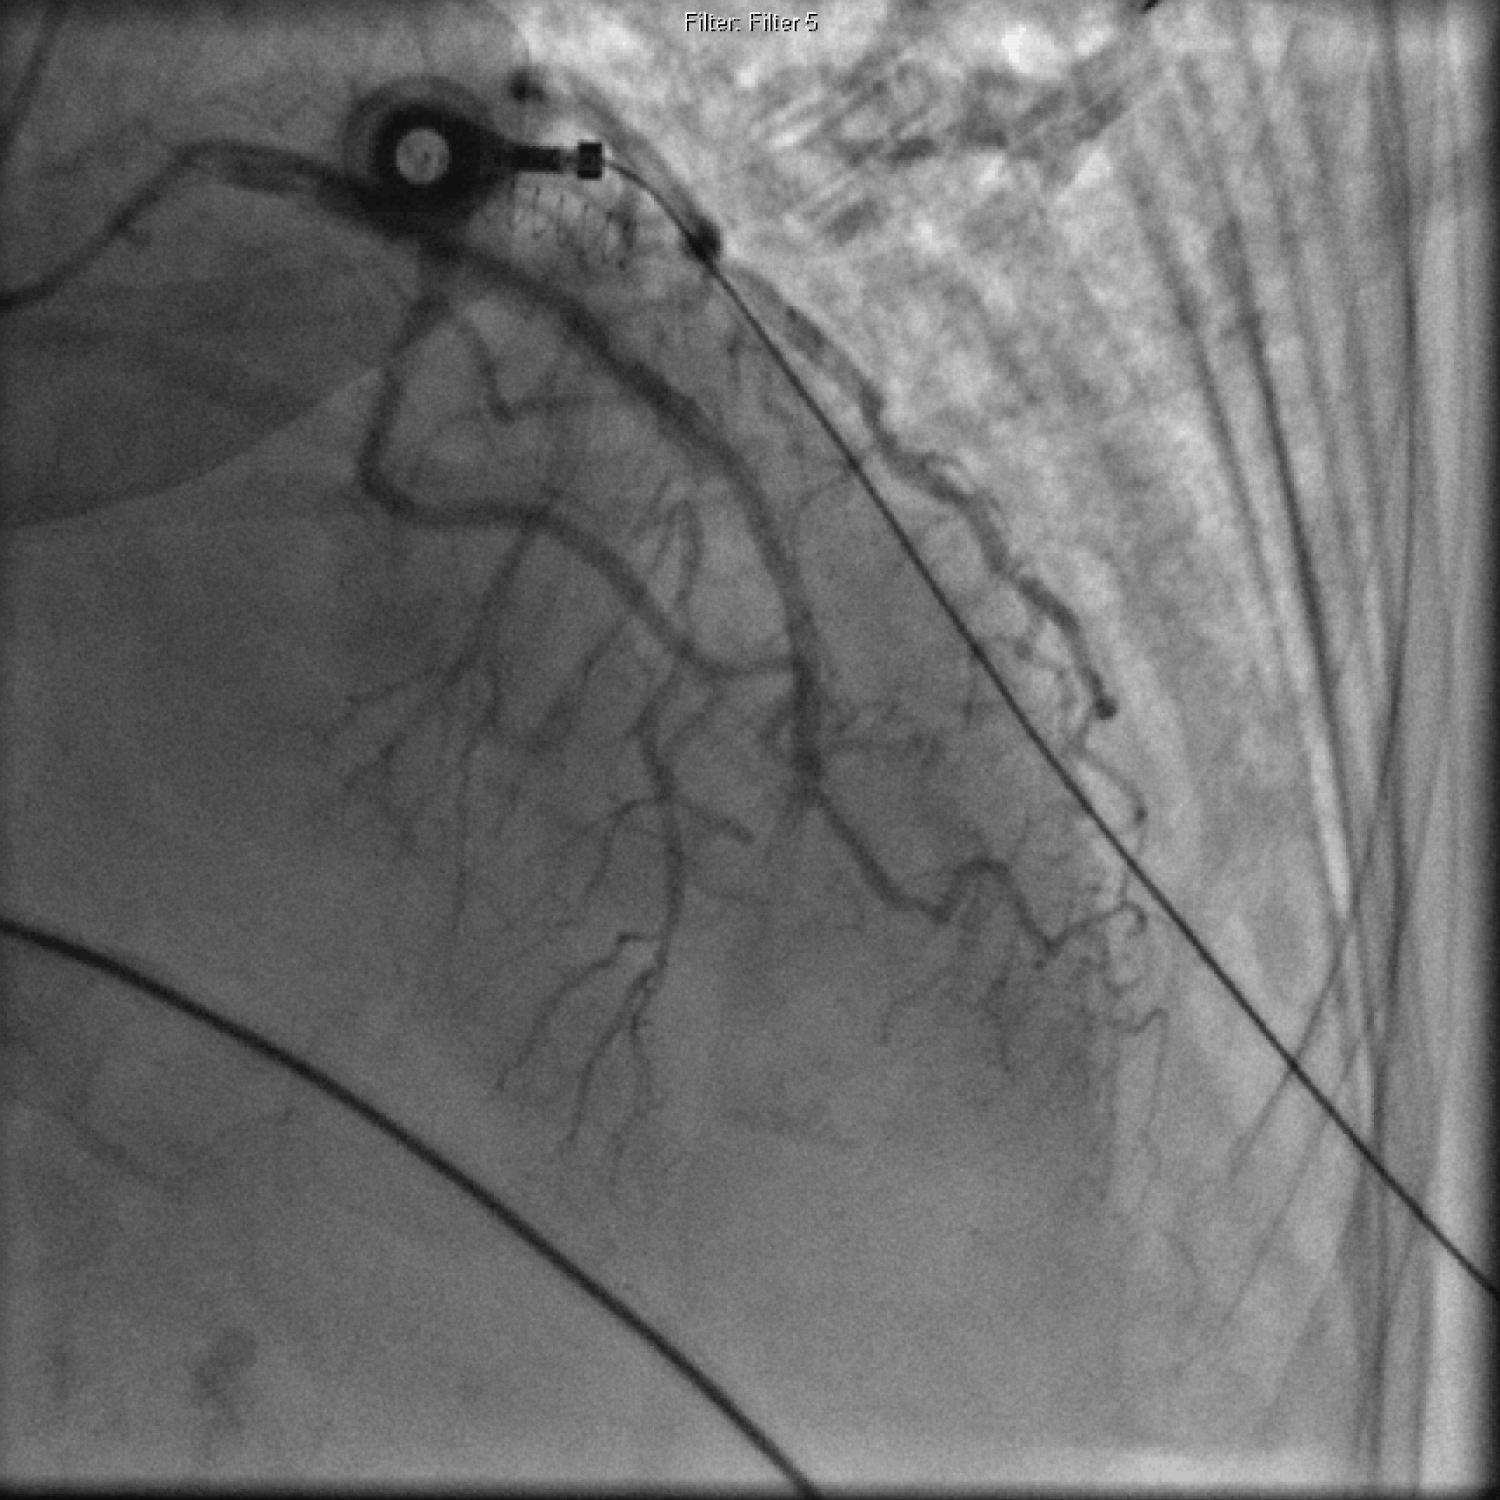

Cardiac catheterization showed 100% distal LAD lesion (Figure 6 and Video 4). Thrombectomy and PCI of the LAD lesion was performed with balloon angioplasty and stent placement but distal flow could not be achieved (Figure 7, Video 5 and Video 6). TTE post procedure showed mild segmental left ventricular systolic dysfunction with hypokinesis of the apex with an ejection fraction of 45% (Figure 8). She was transferred to the intensive care unit for further care.

Figure 6: Coronary angiography showing distal LAD 100% occlusion. View Figure 6